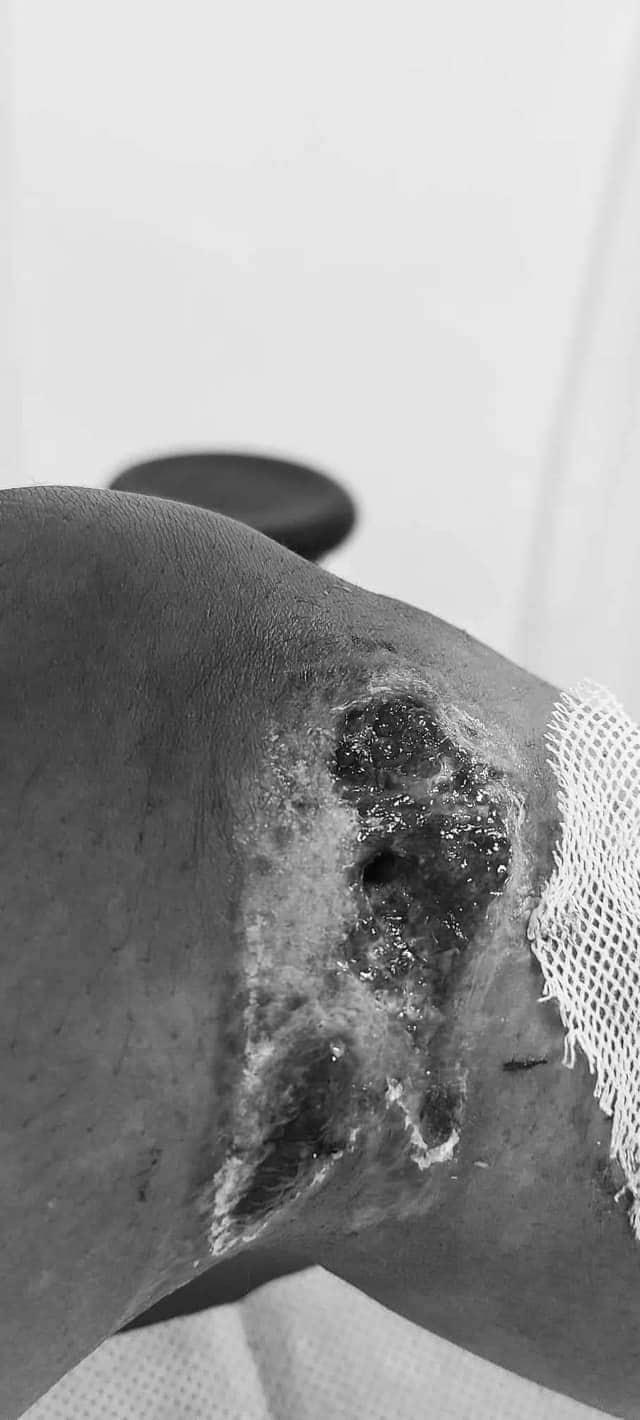

-Охины минь биеийн байдал дунд зэрэг л байна даа. Эмнэлгээс гараад хэд хонож байгаа. Ээж нь охиноо сахиад гэртээ байгаа. Хөлийнх нь шарх аниагүй, өвдөгний гадна талд нь ухаад авчихсан юм шиг том нүх үүссэн. Хөлийнх нь боолтыг авбал дотор талынх нь шөрмөс, судас нь ил харагдаад аймшигтай л байна. Зөөлөн эдийн гэмтэл гэдэг чинь тийм амархан эдгэрэхгүй юм шиг байна лээ. Урьдын адил гүйж, харайгаад явах хүртэл цаг хугацаа орох байх. Одоо өлмий дээрээ ганц нэгхэн алхаж байгаа. Оёдол, шарх нь хөндөгдөөд байгаа учраас бүтэн улаараа гишгэж чадахгүй байгаа. Энэ нь хөнгөн, бэртэл нь бага, биеийн байдал нь сайн гэсэн үг биш.  Одоогийн байдлаар 100 хувь хүний асаргаанд байна. Ямартай ч охиныгоо эдгэрэхийг хүлээгээд л байж байна. Тэр хүртэл миний жаахан охин зовж, шанална гэхээс гол зурах юм. Цаашид гарах үр дагавар, сөрөө нөлөөг нь бодохоос ч айж байна.

-Тийм ээ, хөл нь боолттой охиныг минь харчихаад явсан шинжээч залуу “Хөнгөн бэртсэн” гэсэн дүгнэлт гаргасан байсан. Бид дахин хандаж, шинжээч томилж өгөхийг хүсэхэд мөн л тэр ШШҮХ-ийн шинжээч Даваасүрэнг томилсон байсан. Даваасүрэн шинжээч дахиж ирээд, охины минь хөлийнхөө боолтыг солиулж байгааг харчихаад явсан байна лээ. Гэтэл дахиад л хөнгөн бэртэл гэж гаргасанд гайхаж байна. Яг ямар зорилгоор хүн харахын аргагүй хөлтэй болсон охиныг минь хөнгөн бэртсэн гэж үзээд байгааг ойлгохгүй байна. Угтаа 28 хоногийн дотор эмчилгээ, асаргаа хийлгээд эрүүл болсон хүнийг хөнгөн бэртэл гэдэг юм билээ. Гэтэл миний охин бэртээд 21 хоног болж байна шүү дээ. Эдгэрэх, шарх нь аних, алхах хаа ч байсан юм.

-Хамгийн сүүлчийн шийдвэрийг таван хүнтэй баг гаргах юм билээ. Бид дахин хандаж, таван хүнтэй баг томилж өгөхийг хүссэн. Энэ хүмүүс л хамгийн сүүлийн шийдвэрийг гаргаж өгнө гэсэн үг. Нүдэн дээр ил харагдаж байгаа гэмтлийг үнэн зөвөөр нь гаргаж өгнө гэж итгэж байгаа. Энэ чинь бүхэл бүтэн хүүхдийн ирээдүй, эрүүл мэнд, амьдрал яригдаж байгаа асуудал шүү дээ. Охиныг минь дайрч байгаа бичлэг нуун дарагдаж, олон нийтэд хүрээгүй байсан бол бид хохироод үлдэх байсан. Ямар азаар тэр бичлэгийг олон нийтэд нээлттэй болгосон юм бол доо гэж бодож сууна. Хоёрдугаарт, би охиныхоо гэмтсэн хөлний зургийг шүүх шинжилгээний дүгнэлт  гарахаас өмнө олон нийтийн сүлжээнд цацах ёстой байжээ. Хэрэв тэгсэн бол миний охины шүүх шинжилгээний дүгнэлт үнэнээрээ гарах байсан байх. Үүнд л маш их харамсаж байна. Би хуультай оронд амьдарч байгаа учраас итгэж байсан юм. Ийм жаахан охиныг тэгж их гэмтчихээд байхад хөнгөн гэж дүгнэнэ гэж хэрхэн санах билээ дээ. Энэ хэргийг үнэн зөвөөр л шийдэж өгөөсэй гэж хүсэж байна даа. Охиноо хайрлаад, олны хэл амнаас айхдаа бид чимээгүй байсан. Хэрэг хуучрах тусам биднийг хөсөр хаяж байгаад гомдолтой байна.